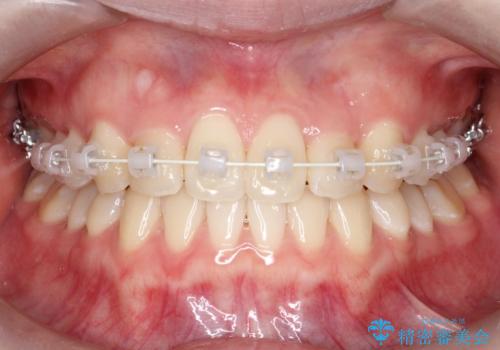

- インビザライン、ワイヤー矯正

ワイヤー矯正とインビザライン矯正を併用することによって、治療期間の短縮と、より良い仕上がりを目指す治療を選択することとしました。

インビザライン(アライナー)矯正とワイヤー矯正のそれぞれの利点を生かした治療を行い、綺麗な歯並びになりました。